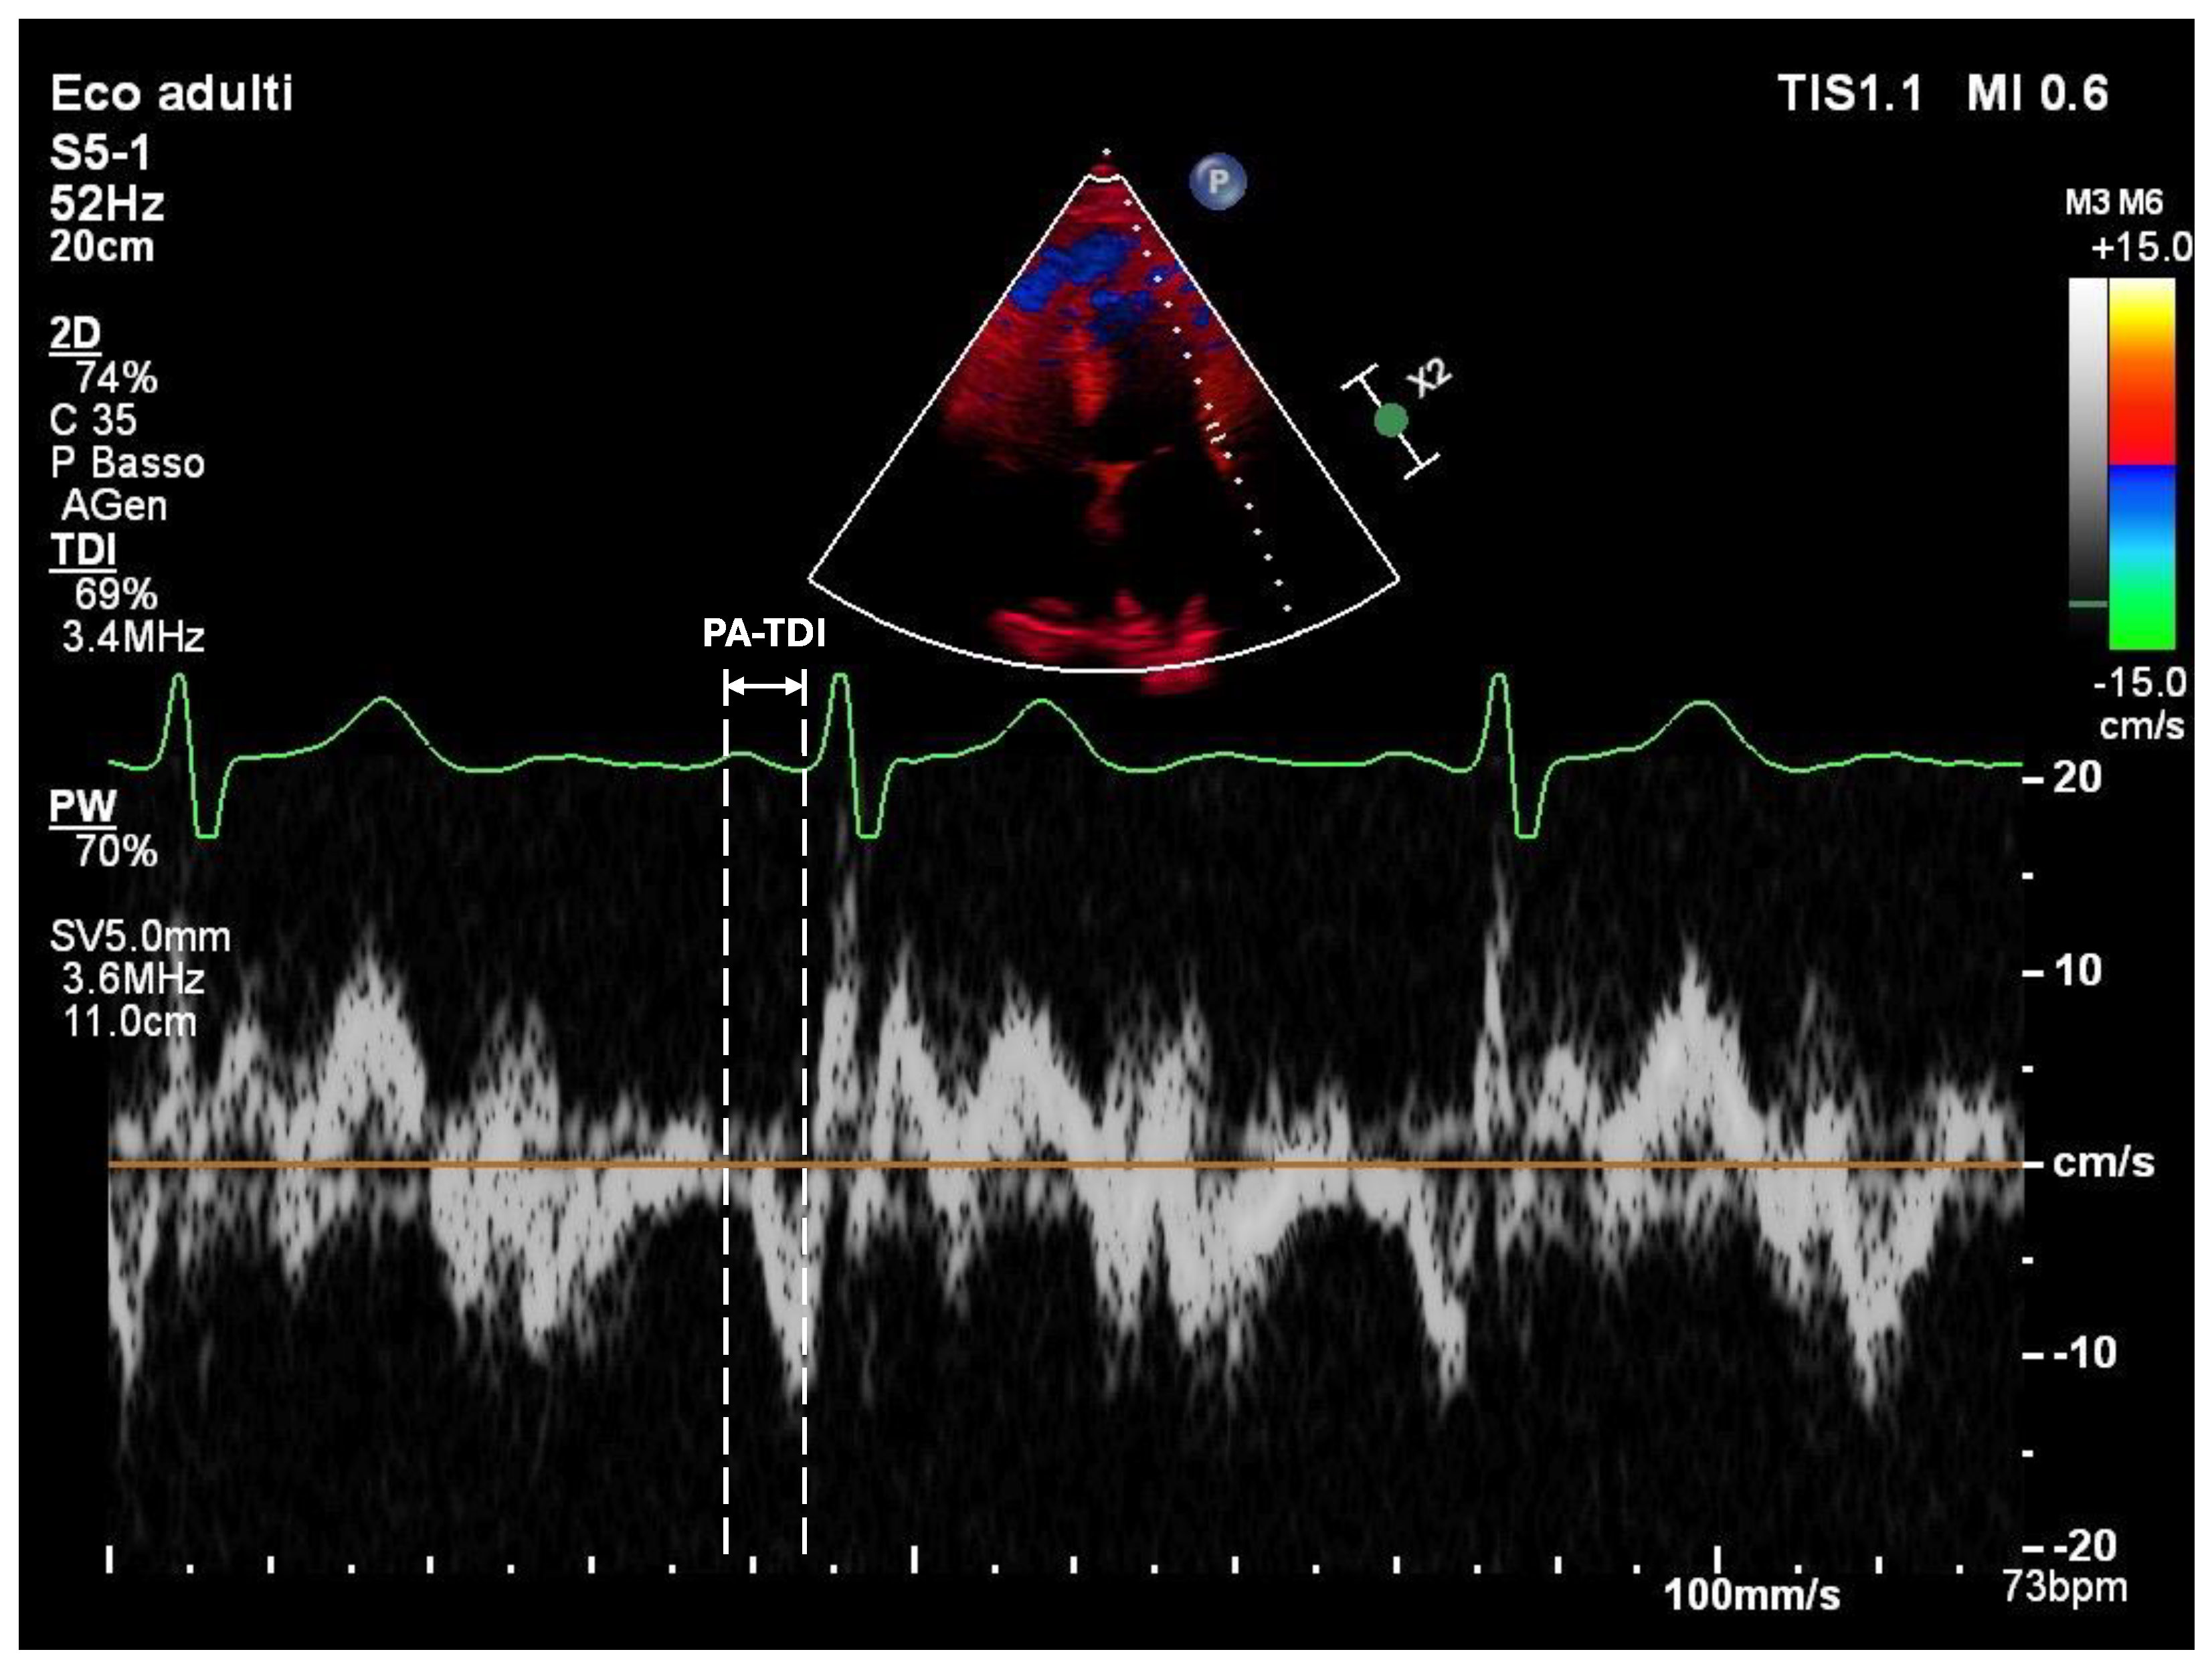

- Atrial Conduction Time (PA-TDI): PA-TDI is calculated as the time interval from the onset of the P wave on a surface ECG to the onset of the A’ wave measured by tissue Doppler imaging at the lateral mitral annulus [22] (Figure 2). This parameter reflects atrial electromechanical delay and serves as an indicator of electrical remodeling. Normal values are usually below 120 milliseconds, while intervals above 150 milliseconds suggest significant conduction slowing, often due to fibrotic tissue or dilated atrial architecture [23]. Prolonged PA-TDI is independently associated with arrhythmia persistence and ablation failure [24].